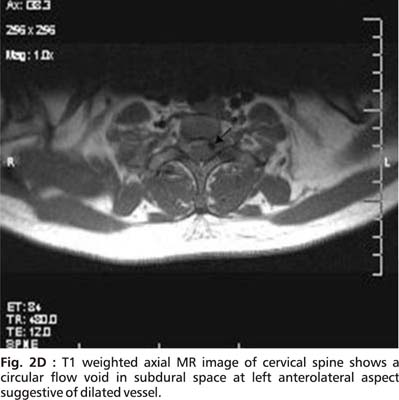

An initial MRI cervical spine revealed cervical cord edema at C5 to C7 ( Fig.1). A repeat MRI done after 15 days showed striking changes in the same area (Fig. 2A, 2B, 2C and 2D).

The cervical MR findings are suggestive of subacute spinal subdural hemorrhage appearing hyperintense on both T1 and T2 images. Serpigenous flow voids were seen on axial sections suggestive of Arterio-Venous malformation (AVM). Unfortunately, a subsequent angiographic study could not be done.